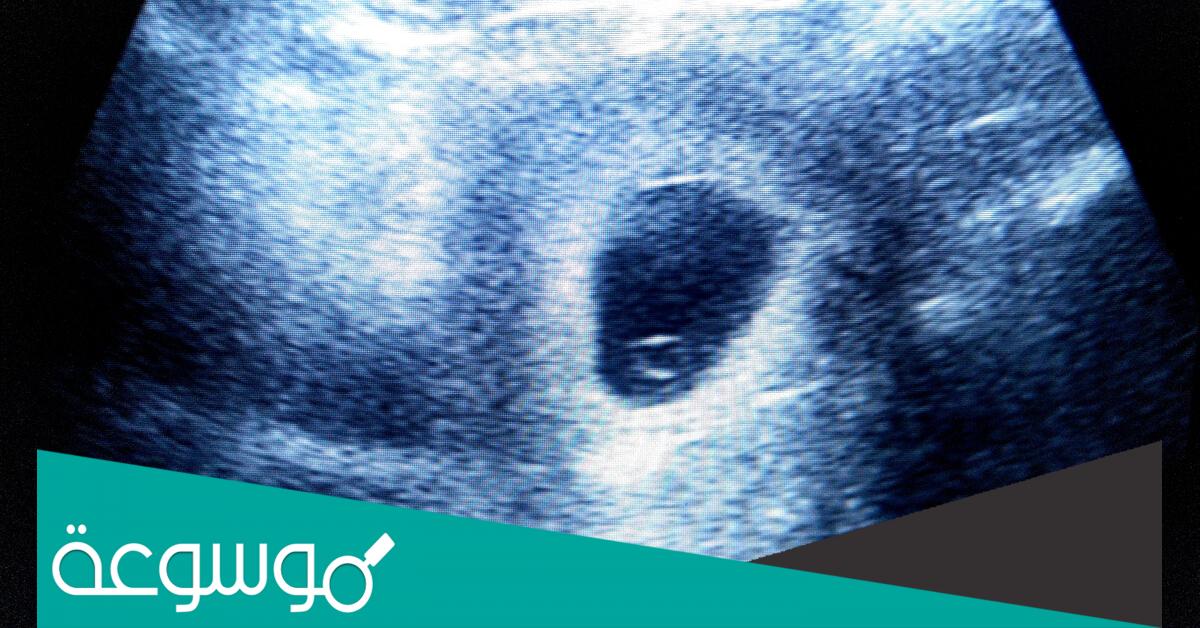

جميعنا يعلم أن الجنين في أول أسابيع الحمل يكون في شكل نطفة بداخل كيس وهذا بشكل محدد وتقريبي يكون الحمل قد وصل إلى أسبوعه الخامس أي مر شهر على حدوث الحمل وبالتالي يستطيع الطبيب والأم رؤيته من خلال الموجات فوق صوتية وهي السونار.

في أغلب السيدات نجد أن الكيس واضح ولكنه فارغ لا يوجد بداخله نطفة وهذا ما يجعلهم يسألون عن متى يتكون الجنين داخل كيس الحمل ولكن هذا ليس مقلق فقد تم الفحص في وقت غير متناسب مع وقت تكون النطفة أي تم في شكل مبكر وهو قبل حلول الأسبوع السادس والسابع وهنا قد نجد الطبيب يطلب من السيدة زيارته بعد مرور أربعة عشر يوم.